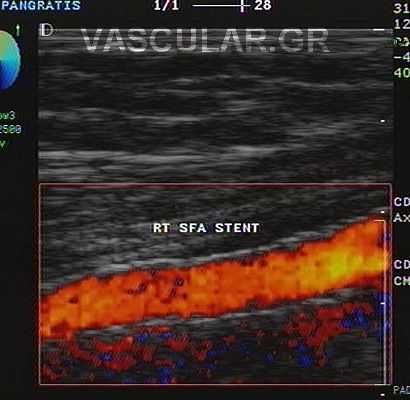

Óôçí ìÜñêï áããåéïðÜèåéá åëÝã÷ïõìå ìå õðåñÞ÷ïõò triplex-doppler äéá ìÝóù ôçò õðåñç÷çôéêÞò Ðáíáñôçñéïãñáößáò.